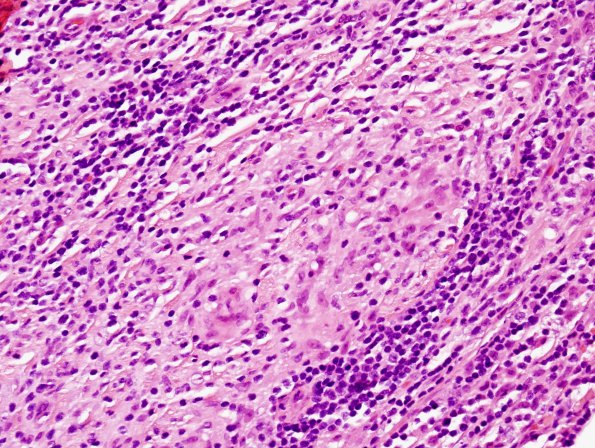

Higher magnification of the endoneurium with prominent inflammation and epithelioid histiocytes lacking multinucleated giant cells. (H&E)